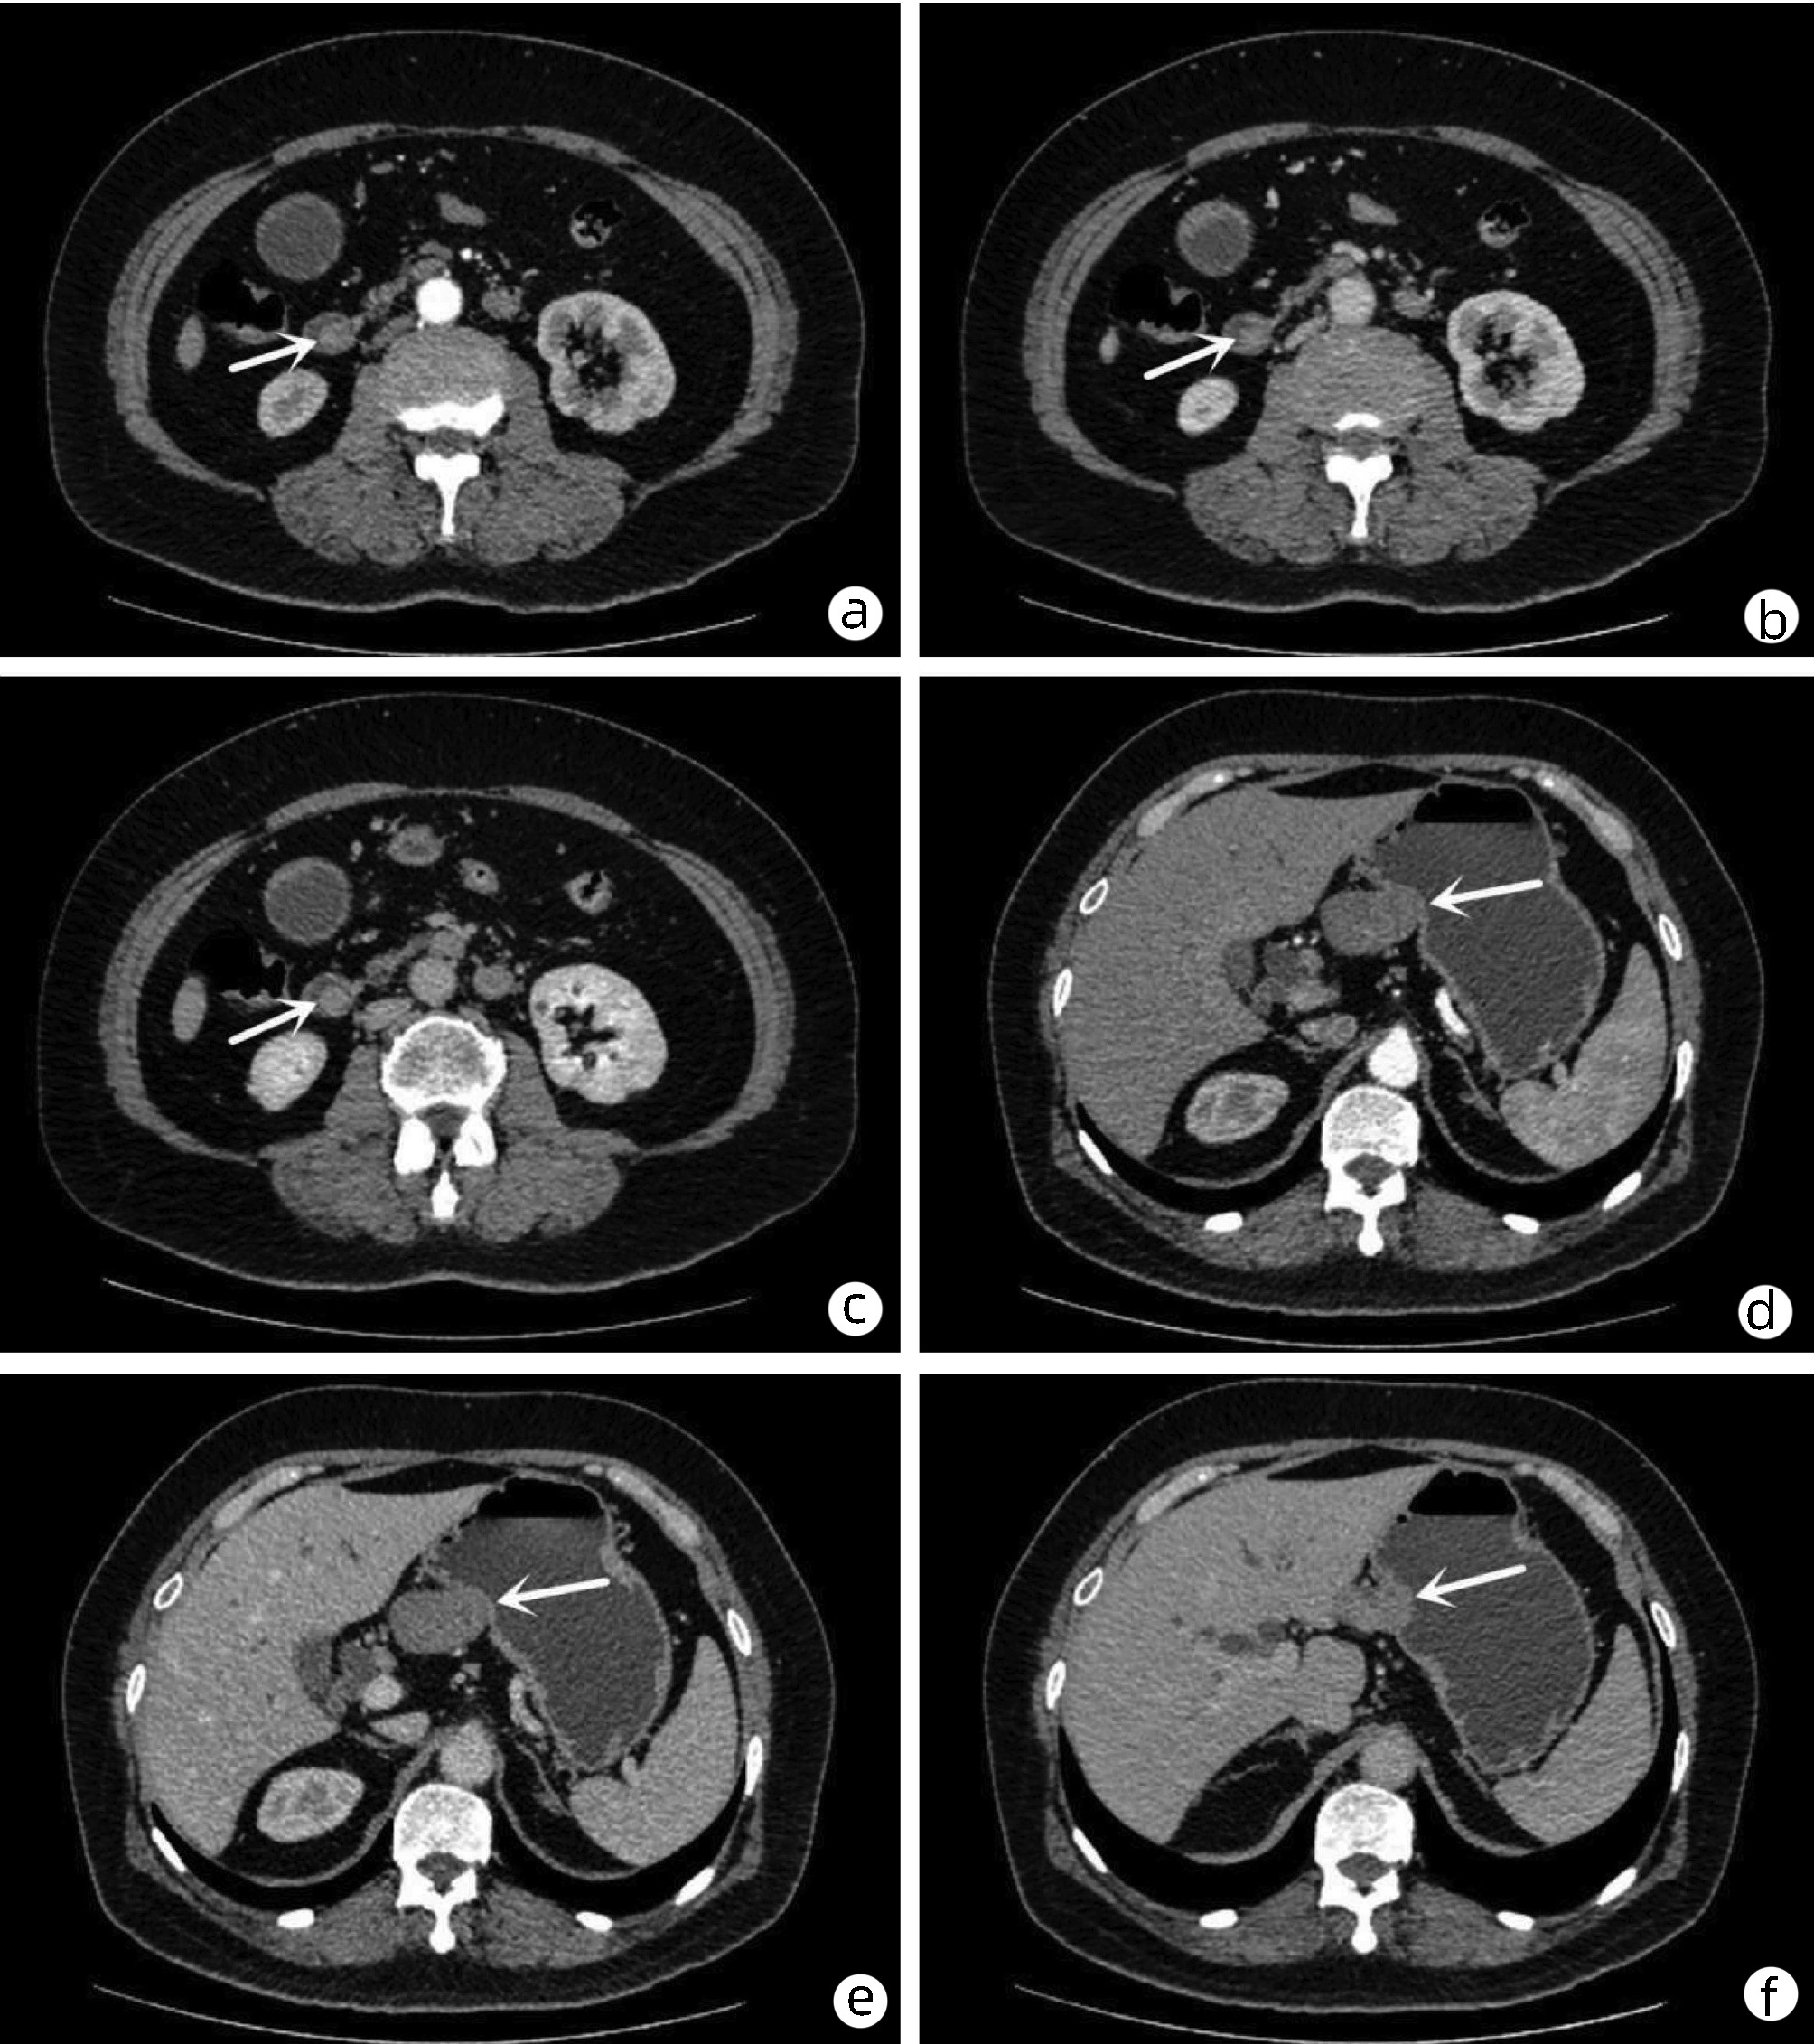

IgG4-related retroperitoneal fibrosis: A case report

Zhaoxia LI, Yang LIU, Nan LI, Zhuhui JI, Guijie XIN

2022, 38(5): 1126-1128. DOI: 10.3969/j.issn.1001-5256.2022.05.030

Abstract(758) HTML (364) PDF (2161KB)(55)

Abstract: